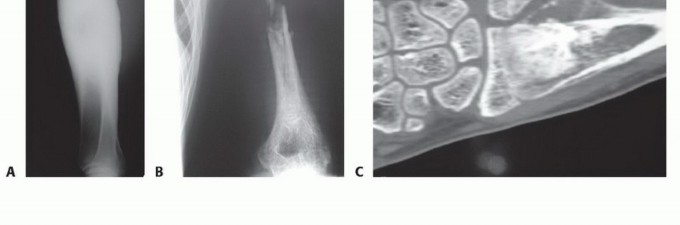

- الأشعة السينية العادية (Plain Radiography): تُظهر صور الأشعة السينية العادية (FIG 4AB) العيب العظمي وحجمه، وتساعد في تقييم بنية العظم المحيطة.

- التصوير المقطعي المحوسب (CTA): يُستخدم التصوير المقطعي المحوسب (FIG 4C) عندما تكون الأوعية الدموية غير واضحة، حيث يوفر صورًا مفصلة للأوعية الدموية في المنطقة المستقبلة.

تصوير عيوب العظام

- أ. صورة شعاعية عادية للظنبوب تُظهر ساركوما عظمية كبيرة منخفضة الدرجة في الجزء الجذعي.

- ب. صورة شعاعية عادية للذراع تُظهر فقدانًا كبيرًا للعظم وكسرًا مرضيًا مرتبطًا بالتهاب العظم والنقي الحاد في جسم العضد.

- ج. إعادة بناء مقطعي محوسب إكليلي للساعد البعيد يُظهر ساركوما عظمية في الكعبرة البعيدة.